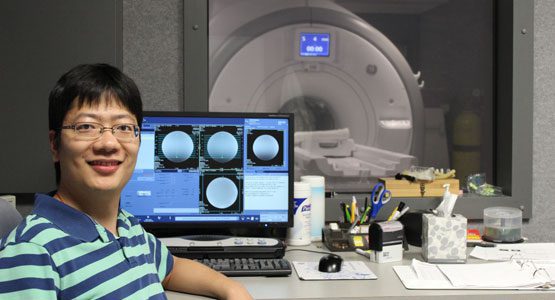

Hao Sun earns 3 Paper Awards for medical imaging research

Hao’s research is focused on improving the quality of images from magnetic resonance imaging pulse design.